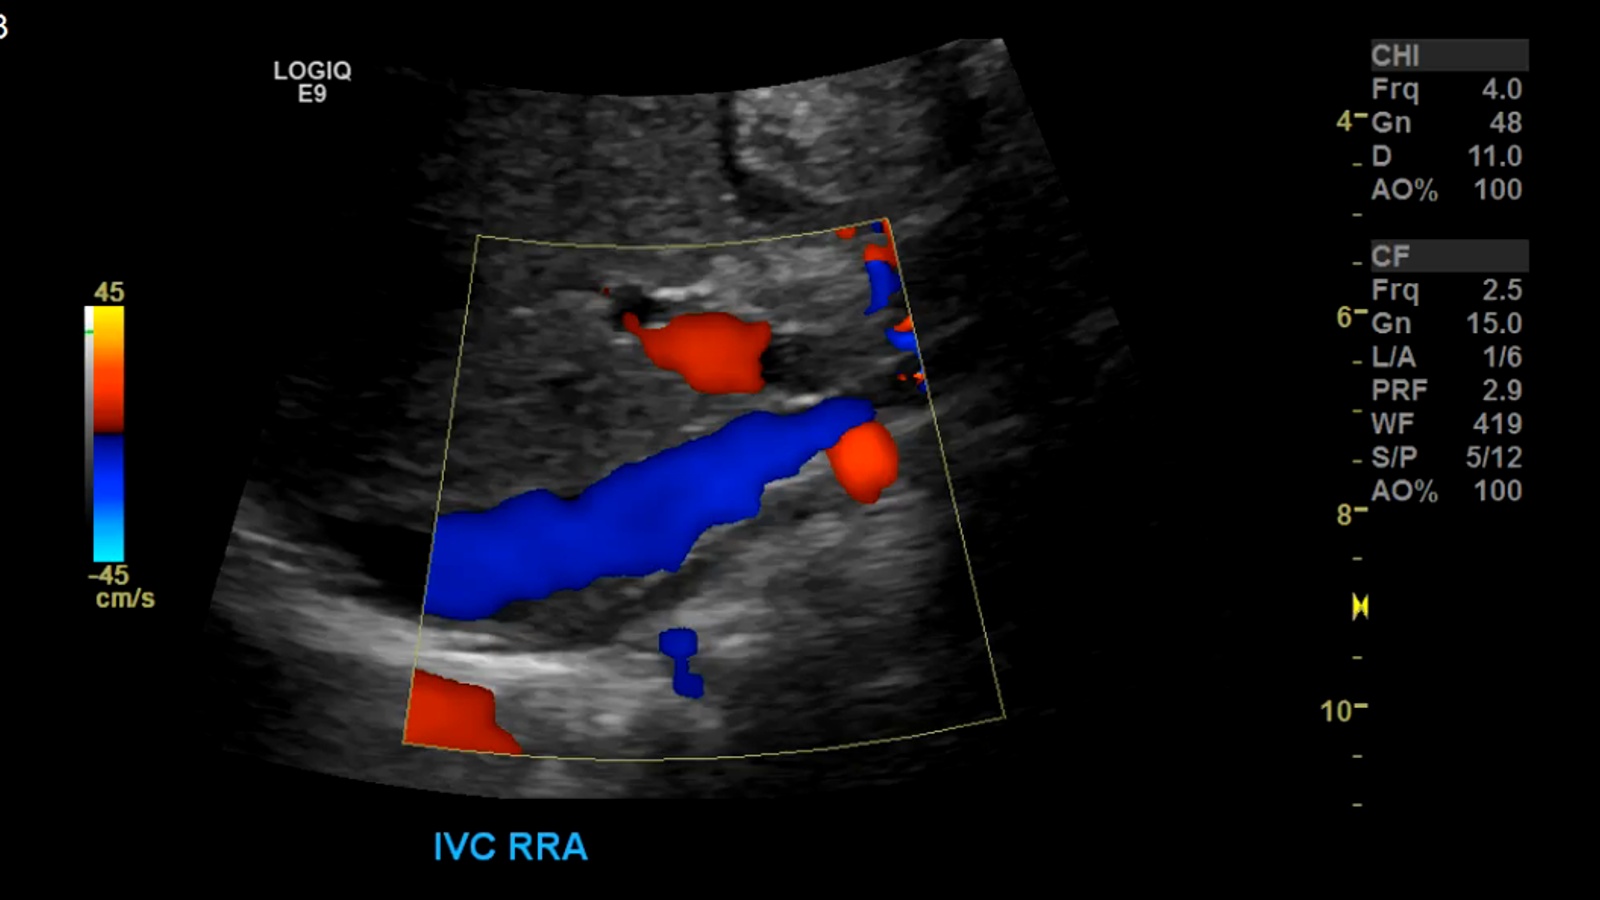

The renal arteries are paired blood vessels that arise from the mid aorta. The right renal artery is typically longer than the left due to the anatomical location of the aorta being more lateral to left of the body. It courses behind the IVC, which can be used as a window in difficult patients.

Inferior Vena Cava

The inferior vena cava is the largest abdominal vein receiving deoxygenated blood from the Kidneys, Liver, Spleen and Gastrointestinal system among others.

As stated before the RRA will be located posterior to the IVC. The LRV will be sandwiched between the Aorta and SMA.